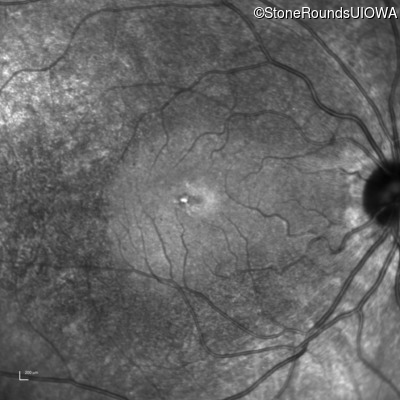

Age at visit: 24 years

OD OS

This 24 year old man has recently noticed that he sees more poorly than his peers in movie theaters.